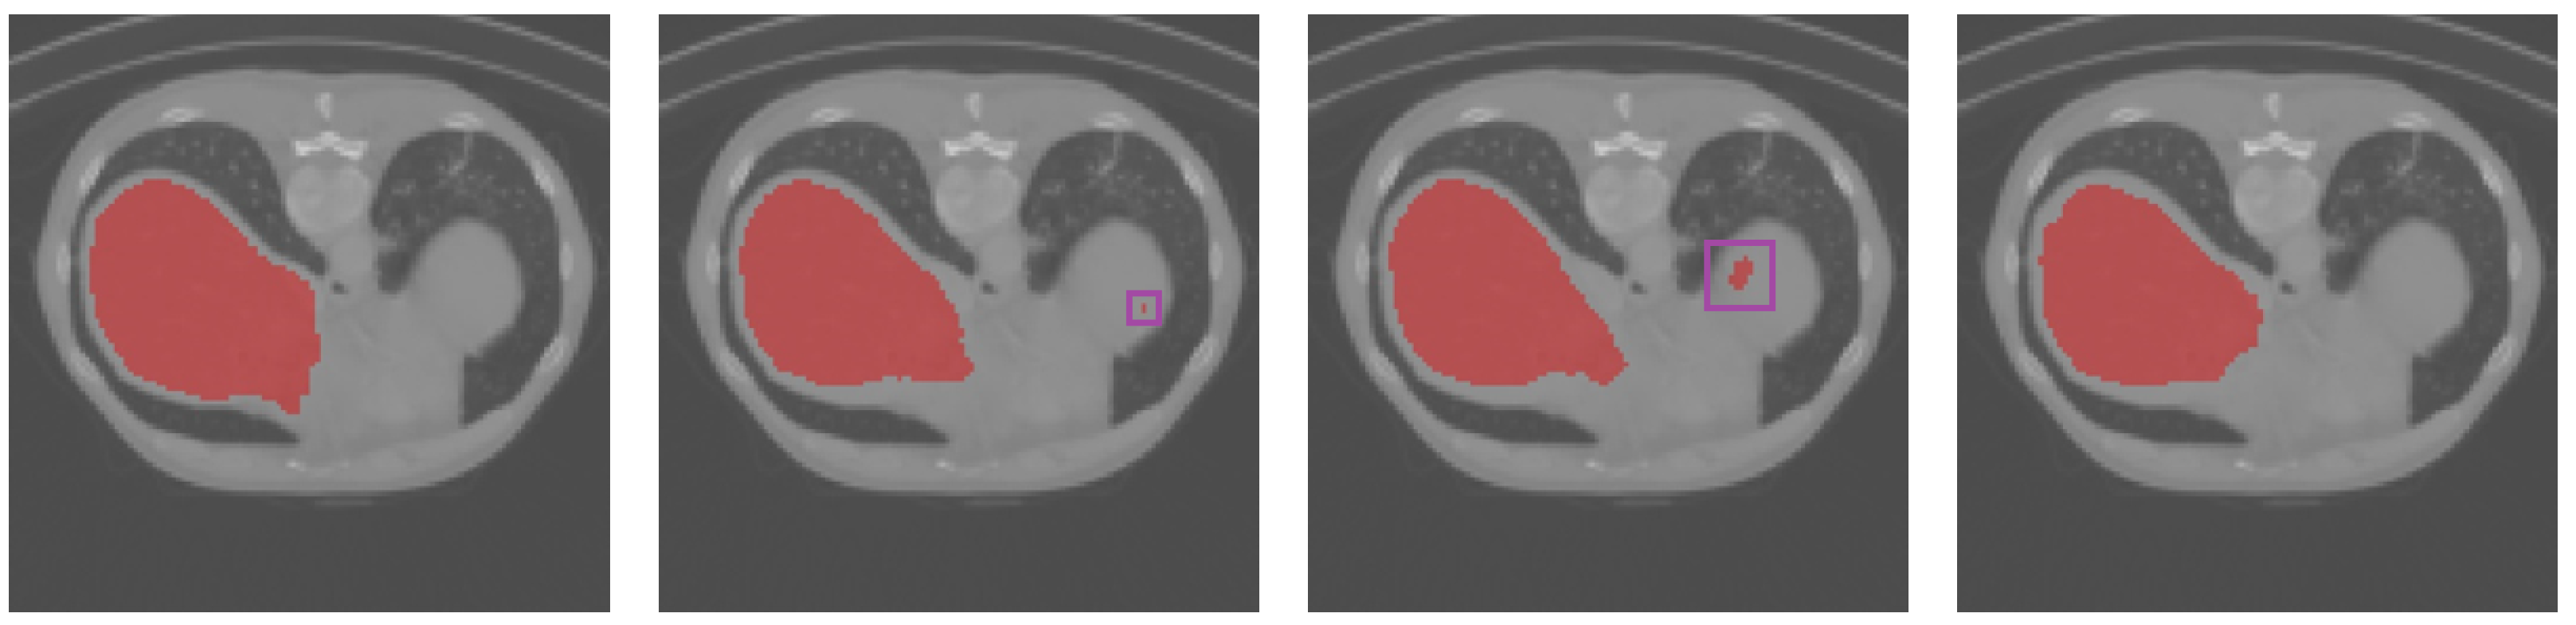

3.4. Results Obtained on the Colonoscopy Dataset

| Dice | TPR | TNR | HD95 | |

|---|---|---|---|---|

| U-Net | 60.12% | 56.72% | 99.93% | 4.99 |

| UNet++ | 68.93% | 59.93% | 99.97% | 6.32 |

| Att-UNet | 72.37% | 61.77% | 99.98% | 5.74 |

| Focus-UNet | 68.13% | 55.16% | 99.97% | 7.01 |

| SAB-Net | 74.31% | 63.05% | 99.98% | 4.24 |